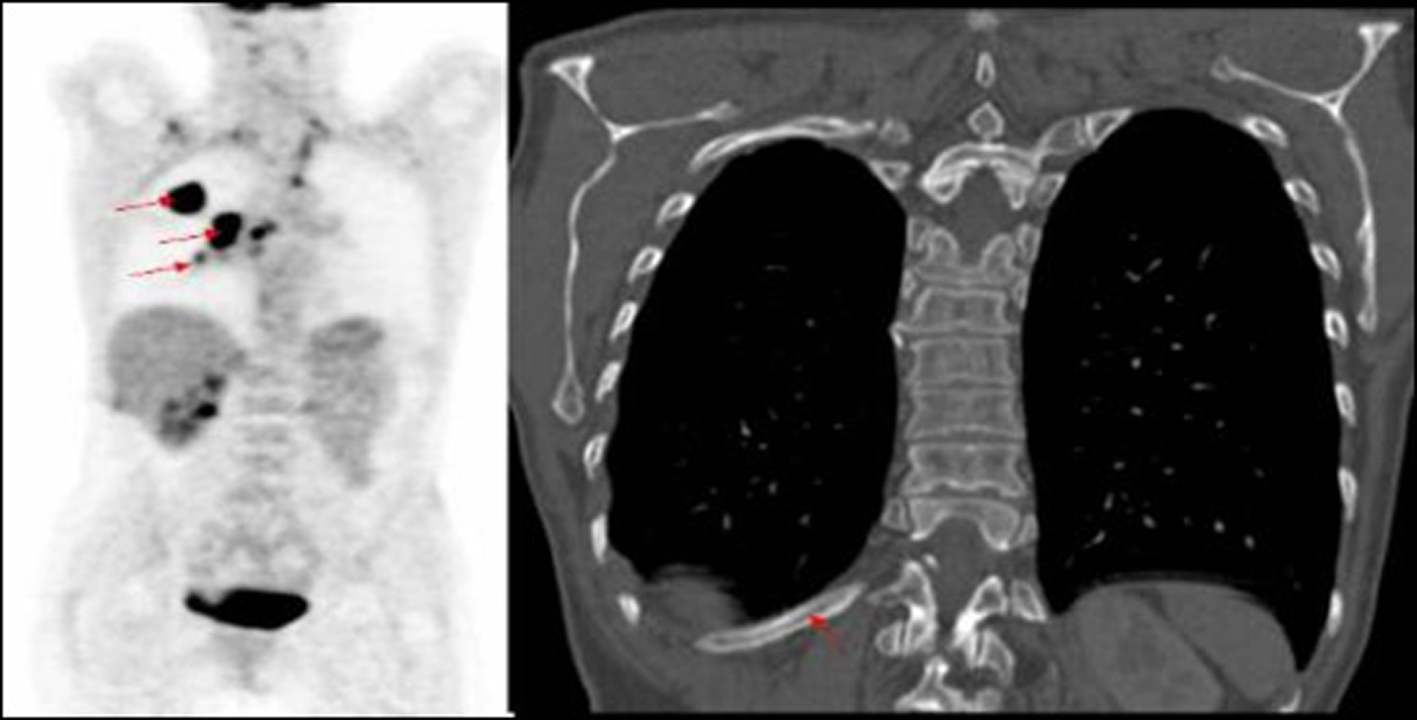

In our study nearly half of the in field metastasis were identified by two observers (Fig. 1). Most of the missed in field metastasis were bony involving the ribs, acromion and spine (Fig. 2, 3, 4). This could be explained by a number of reasons. Firstly it is easier to overlook a small bony metastasis especially in the ribs. Secondly, MIP (maximum intensity projection) reconstructions helps to depict the metastatic deposits better. If one does not routinely perform these, it might account for the missed deposits.

![]() Click for large image | Figure 2. PET image of right lung tumour with right hilar mass and increased uptake in mid thoracic vertebra, not identified on corresponding CT of primary lung cancer. |